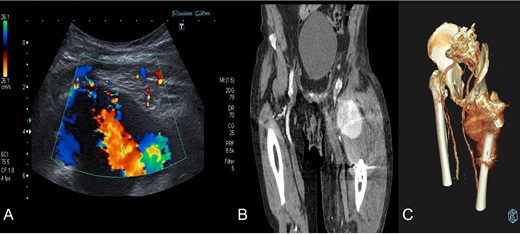

Diagnosis confirmation by Doppler ultrasound (A), shows hypoechoic lesion with turbulent flow inside with 5–6 cm of maximum diameter; and CT angiography (B) and three-dimensional reconstruction (C) that confirm a lateral circumflex artery pseudoaneurym branch of the deep femoral artery of 7,3 × 6,7 × 6 cm size.